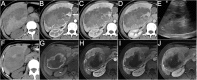

Results: More females (14/22) were affected with the mean age of 47.1 years. Most patients (17/22) were asymptomatic and the routine laboratory tests were normal. More tumors occurred in the right lobe (13/22) with a mean diameter of 76.7 mm. Surgery was performed in 21 patients, and biopsy was performed in 1 patient. Immunohistochemical studies showed the expression rate of HMB-45 and Melan A was 100% (22/22) and 86.4% (19/22) within the tumor cells. The pathology diagnoses were angiomyolipoma (n = 18), lymphangioleiomyoma (n = 2), clear-cell myomelanocytic tumor of falciform ligament/ligamentum teres (n = 1), and not otherwise specified (n = 1). Fifteen cases were classified as uncertain malignant potential (n = 13) or malignant (n = 2). CT, MRI and ultrasound features included well-defined margins (19/22), internal heterogeneity (20/22), arterial enhancement (20/22), dysmorphic vessels (17/22), fat (9/22), hemorrhage (3/22), necrosis (8/22), and calcification (2/22). The diagnostic accuracy was only 27.3% (6/22). No local recurrence or metastasis was found in the follow-up patients (12/22).

Conclusions: On CT, MRI and ultrasound images, most hepatic PEComas are well-defined, heterogeneous, arterial enhanced masses with dysmorphic vessels, with or without fat, especially in middle-aged females. With the potential to be malignant, timely surgical resection and long-term follow-up may be helpful for improving the prognosis.